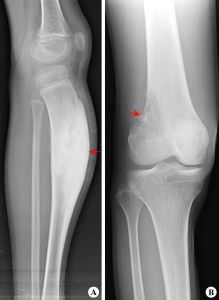

X線檢查

骨刺X線平片不僅為骨質增生的常規檢查方法,有的學者還認為骨質增生的X線檢查是追蹤病情變化的金標準。

骨刺的X線片可分為五級:

0級:無改變;

1級:輕微骨贅;

2級:明顯骨贅,關節間隙正常;

3級:骨贅外關節間隙中度狹窄;

4級:骨贅外關節間隙嚴重狹窄,伴軟骨下骨硬化。

拍膝關節片時,病人應取站立位拍前後位和側位片,髖關節和手關節可只拍前後位片。在早期階段,X線片大多正常,中晚期可見關節間隙不對稱性狹窄、關節面下骨硬化和變形、關節邊緣骨贅形成,關節面下囊腫和關節腔游離液體等。

骨質增生的x線特點為:關節面硬化變形;關節鼠;關節邊緣骨贅;關節間隙狹窄,如在膝關節,可小於3毫米;軟骨下囊性變,其邊緣分界清楚;骨變形或關節半脫位。